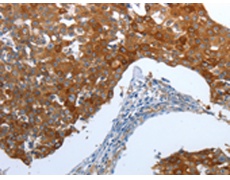

IHC positive control: |

Human breast cancer and Human thyroid cancer |